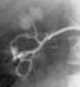

Percutaneous stone removal

Kidney stone disease, also known as nephrolithiasis or urolithiasis, is when a solid piece of material (kidney stone) develops in the urinary tract. Kidney stones typically form in the kidney and leave the body in the urine stream. [Source: Wikipedia ]